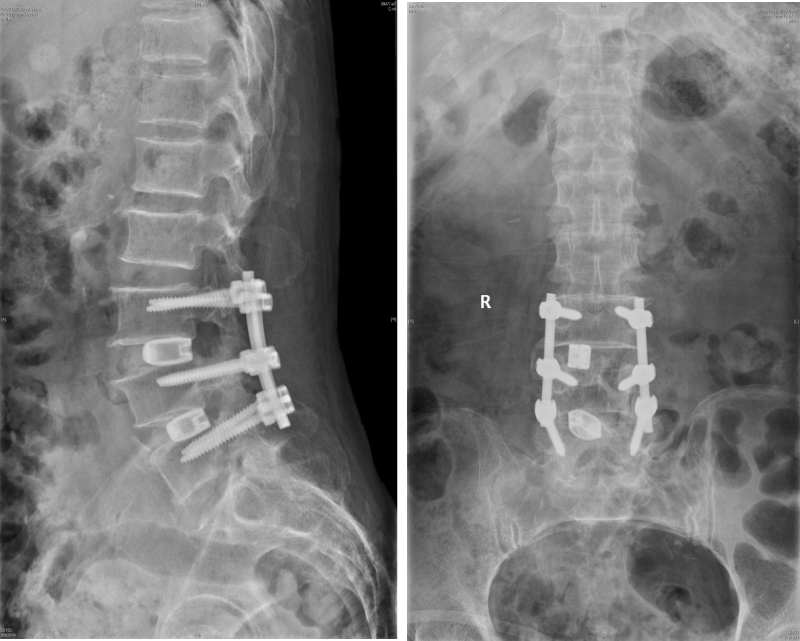

术后

术后DR(王奶奶)